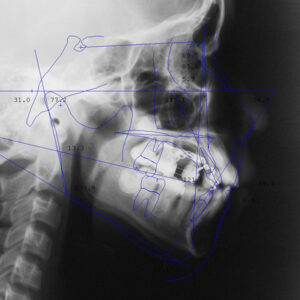

セファロレントゲン

セファロレントゲンは、主に歯列矯正の計画を立てる際に使われるレントゲンです。

頭部の骨格や歯列の位置関係を詳しく確認できるため、矯正治療の計画をより詳細に立てることができます。

特に、外科的矯正や複雑な歯列不正のケースでは、セファロレントゲンによる情報が治療の経過に重要な役割を果たします。